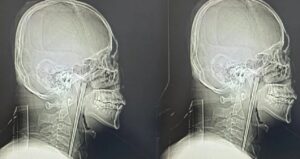

46 yaşındaki bir adam, sekiz yıl önce yuttuğu 12 santimetrelik metal yemek çubuğuyla yaşamaya devam etti. Olay, Çin’in Liaoning eyaletindeki...